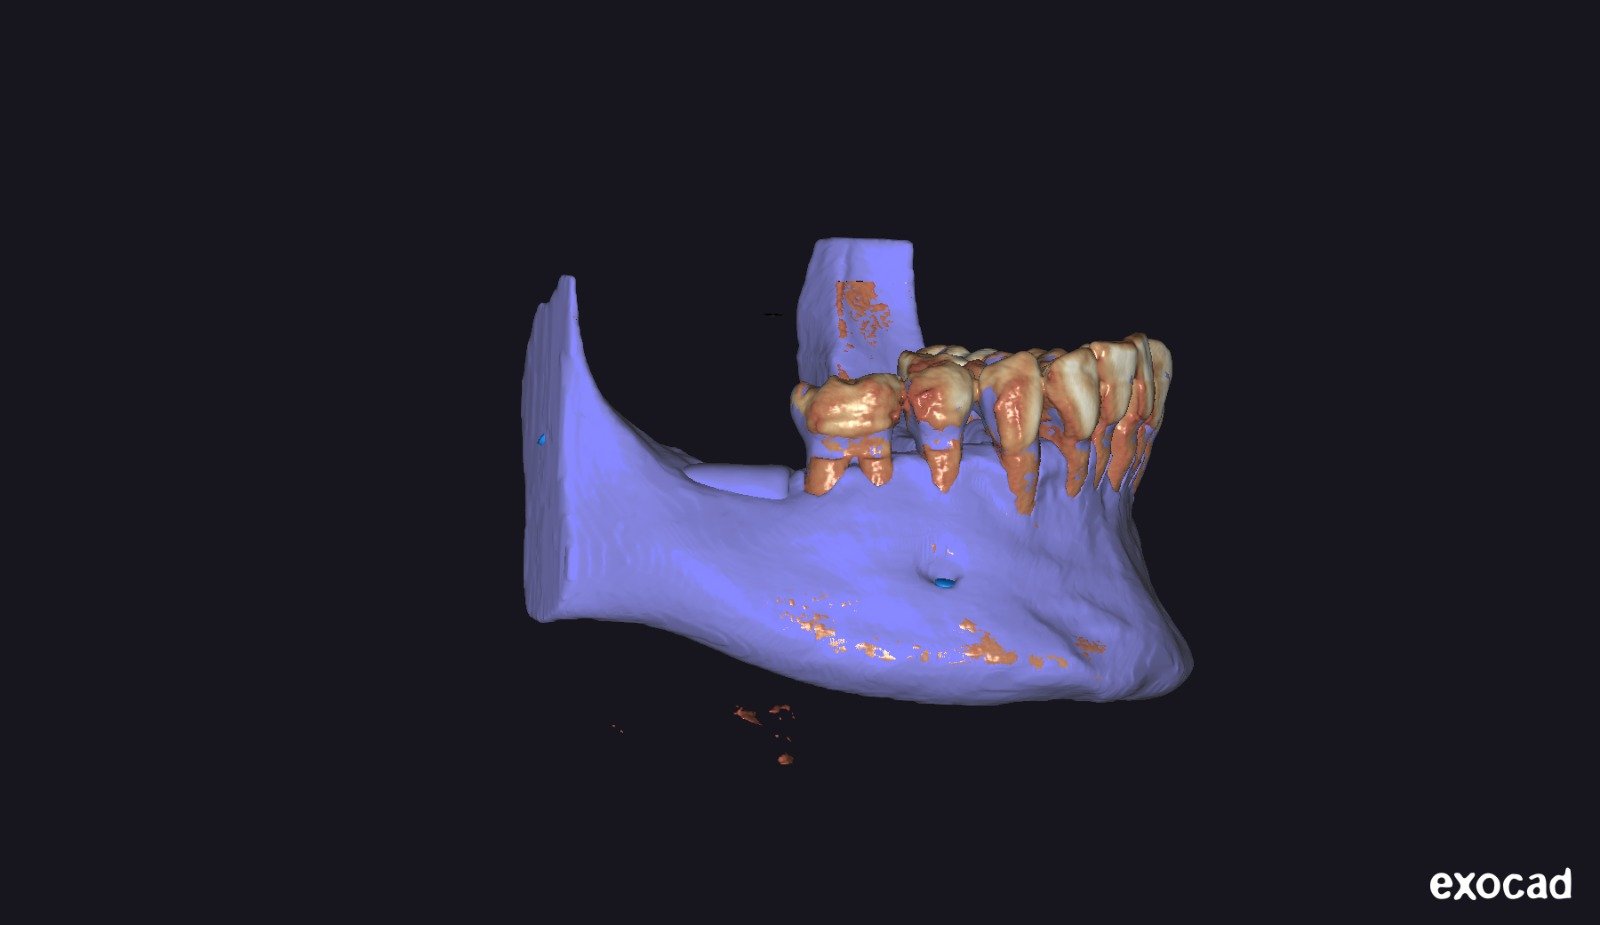

• Introducción al flujo digital en ROG.

• Integración de archivos DICOM, STL y PLY.

• Software utilizados en el protocolo:

• BlueSkyPlan: diagnóstico, segmentación y análisis del defecto.

• Exoplan / Exocad: diseño digital aplicado a la regeneración.

• Meshmixer: ajustes, correcciones y optimización del diseño.

• Segmentación ósea y dental.

• Generación del defecto virtual.

• Control tridimensional del volumen a regenerar.

• Ventajas del diseño realizado por el propio cirujano.